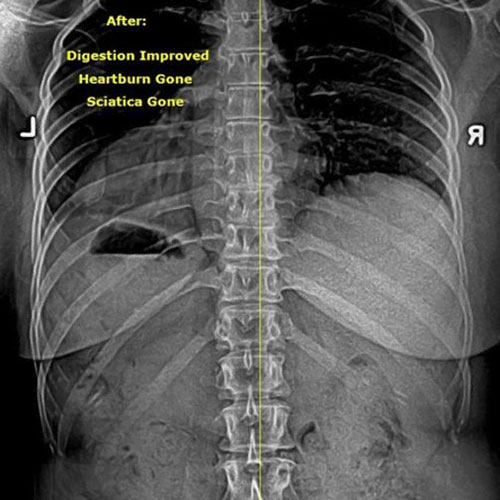

BEFORE & AFTER X-Rays:

SEEING REAL SPINAL CORRECTION

At Champion Wellness, we don’t just aim to help patients feel better — we focus on correcting the structural cause of pain and dysfunction. One of the most powerful ways we do that is through before-and-after X-ray analysis.

After Corrective Chiropractic Care: Following a customized course of corrective chiropractic treatment, repeat X-rays demonstrated measurable improvement in cervical alignment. More importantly, those structural changes translated into real-life results — reduced pain, improved function, and a return to daily activities with confidence.